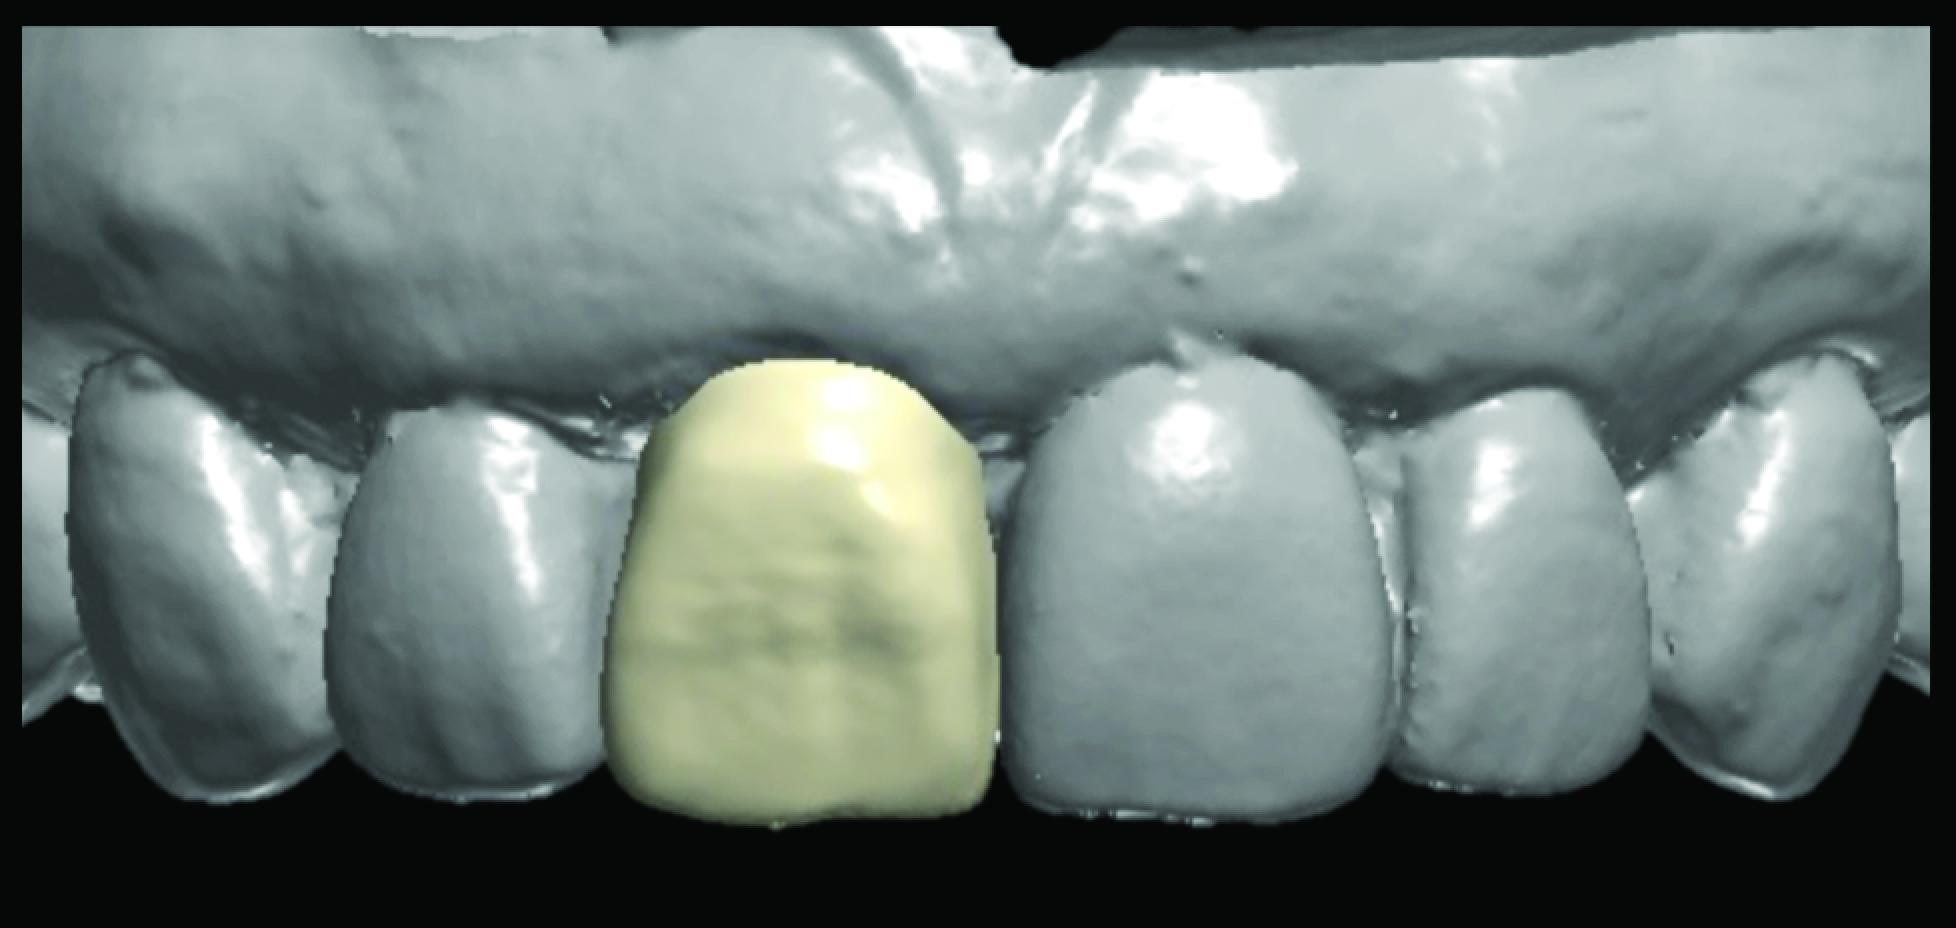

The prosthetic components of the case also were planned at this time. The Simplant file registering all of the positional attributes of the implant was then imported into the Atlantis Abutment software by selecting the Immediate Smile protocol option. This allows a final abutment to be designed from the proposed implant plan. A fully anatomic patient-specific abutment in gold-shaded titanium was selected to achieve optimal soft tissue and prosthetic support.13 The digital file representing the abutment was then exported via an Atlantis Core File and imported into the 3Shape software to design an acrylic resin interim prosthesis. The surgical guide, patient-specific abutment, and interim prosthesis crown were all manufactured and returned prior to the surgical date (Figure 6).

The patient returned for her surgical visit and consent was obtained. Tooth No. 8 was extracted with the aid of periotomes maintaining the integrity of the buccal plate. The socket was curetted and irrigated with sterile saline and the Simplant SAFE Guide was placed. The assessment of the surgical guide’s intimate fit to the teeth was verified by creating occlusal and proximal windows, allowing for visual inspection to assure the guide was seated (Figure 7). The OsseoSpeed EV guided surgical kit (Dentsply Sirona Implants) was used with full depth and location drilling control. The implant was placed through the guide to its proper depth (Figure 7). An insertion torque of 35 Ncm was achieved and verified by the surgical motor, allowing for adequate initial stability for immediate loading. The timing of the implant was attained by assuring the large notch on the implant driver lined up perfectly with the channel index line on the surgical guide (Figure 8 through Figure 10). Due to the immediate nature of the implant placement, a facial gap was evident between the implant and the alveolar process. A xenograft material (Bio-Oss, Geistlich Biomaterials, geistlich-na.com) was placed to fill this gap according to established protocols.14 The Atlantis custom abutment was then placed in its proper position and the seating was verified with digital radiography. The abutment was torqued to 25 Ncm, as per the manufacturer’s specifications (Figure 11). The interim prosthesis was then placed onto the abutment and slight adjustments were made. A final custom stain and glaze was placed on the interim prosthesis crown using Lite Art coloring pastes (Shofu Dental Corporation, shofu.com). The provisional was cemented with TempBond NE (Kerr, kerrdental.com) and was relieved of any excursive contacts. The patient was given post-operative instructions and left in extremely high spirits (Figure 12).